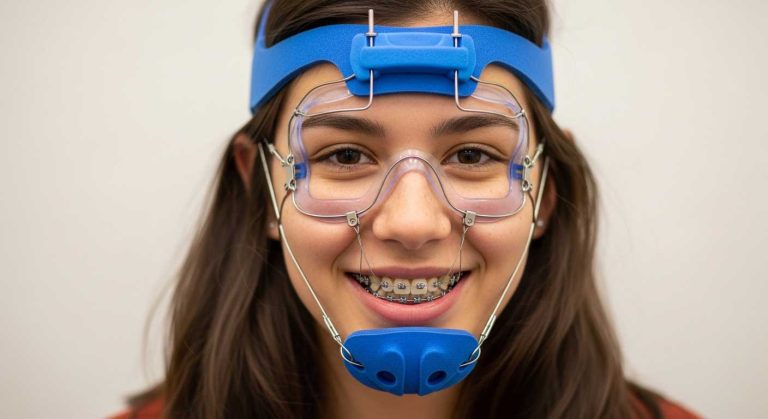

درمان ارتودنسی یک سرمایه گذاری بلند مدت برای زیبایی و سلامت لبخند شما است. هدف از این درمان، اصلاح ناهنجاری های فک و دندان و دستیابی به یک لبخند ایده آل است. اما موفقیت این مسیر تنها به تخصص پزشک و دستگاه های ارتودنسی بستگی ندارد.

سبک زندگی و عادات روزمره بیمار، نقشی حیاتی در نتیجه نهایی ایفا می کند. تاثیر سیگار و قلیان بر درمان ارتودنسی یک واقعیت علمی اثبات شده است که می تواند تمامی زحمات شما و متخصص ارتودنسی را به خطر اندازد. از افزایش التهاب لثه گرفته تا کند شدن حرکت دندان ها، سیگار و قلیان دشمنان اصلی یک درمان موفق هستند. در این مسیر، مشاوره ارتودنسی با یک متخصص مجرب می تواند به شما کمک کند تا با آگاهی کامل بهترین تصمیم را برای سلامت خود بگیرید.

حرکت دندان ها در ارتودنسی یک فرآیند بیولوژیک پیچیده است که به تحلیل و بازسازی استخوان اطراف ریشه دندان وابسته است. این فرآیند نیازمند جریان خون کافی و سلامت بافت لثه و استخوان است. تاثیر سیگار و قلیان بر درمان ارتودنسی دقیقاً در همین نقطه نمایان می شود.

نیکوتین موجود در دود سیگار باعث انقباض عروق خونی می شود و جریان خون به لثه ها را کاهش می دهد. این کاهش خون رسانی، توانایی بدن برای ترمیم و بازسازی بافت استخوانی را مختل کرده و در نتیجه، حرکت دندان ها کندتر از حد انتظار صورت می گیرد. به همین دلیل، افرادی که دخانیات مصرف می کنند، اغلب با طولانی تر شدن دوره درمان خود مواجه می شوند. این موضوع اهمیت ترک دخانیات برای دستیابی به نرمال بایت را برجسته می سازد.

نقش متخصص ارتودنسی در مدیریت بیماران سیگاری

یک متخصص ارتودنسی باتجربه، نقش مهمی در آگاه سازی و مدیریت بیمارانی دارد که دخانیات مصرف می کنند. متخصص باید به وضوح تاثیر سیگار و قلیان بر درمان ارتودنسی را برای بیمار توضیح دهد و او را از خطرات و عوارض احتمالی آگاه سازد.

ارائه اطلاعات در مورد طولانی تر شدن درمان، افزایش هزینه ها، مشکلات زیبایی و ریسک بالای بیماری های لثه می تواند انگیزه ای قوی برای ترک یا کاهش مصرف باشد. همچنین، یک متخصص ارتودنسی در قلهک می تواند با آموزش روش های صحیح بهداشت و نظارت دقیق تر، به بیمار در کنترل عوارض کمک کند.